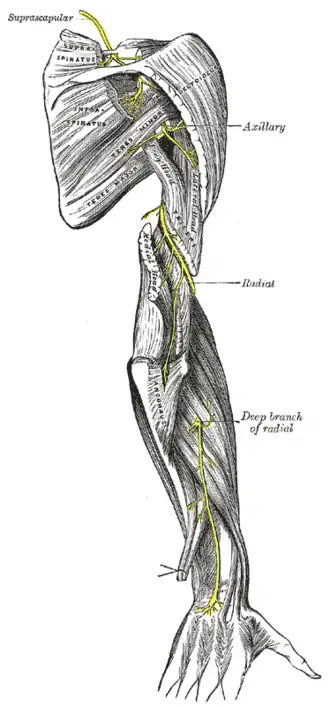

Suprascapular and axillary nerves of right side, seen from behind. (Teres minor is visible at center.)

Suprascapular and axillary nerves of right side, seen from behind. (Teres minor is visible at center.) -

The suprascapular, axillary, and radial nerves.

The suprascapular, axillary, and radial nerves. -